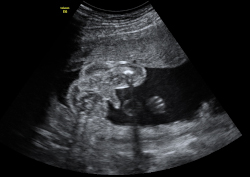

Imagen ecográfica de la dilatación de asas intestinales -marcadas con un asterisco (*)- por causa de una obstrucción en un feto de 29 semanas.

Dilatación de asas intestinales

Imagen ecográfica de la dilatación de asas intestinales -marcadas con un asterisco (*)- por causa de una obstrucción en un feto de 29 semanas. Está anomalía se diagnostica con frecuencia después de la semana 20. Ecografía Embarazo 2D y 3D - SEMANA 20 Ecografía Embarazo 4D - SEMANA 20